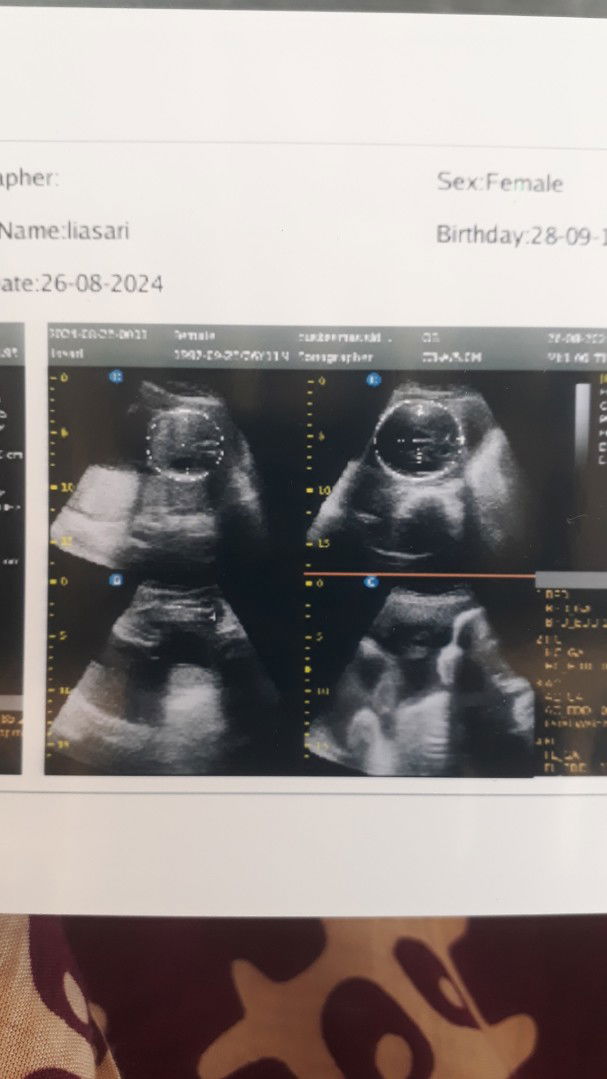

Bun hamil 7mg kok belum kerasa detak jantung ya,apa memang belum ya..?

biasanya blm say nanti 9 mggan baru pas USG kedengeran dekat jantungnya , kalo pake dopler yg manual dan kita merasakan kedutan itu di usia 12 mggan lebih

biasanya klo usg biasa blm keliatan bun krn djj pasti tipis bgt. tpi klo bunda minta ke dokter utk usg transvaginal psti udh kedengeran bun djj nya

aku kemaren habis usg bun, usianya juga udah 7 minggu dan udah ada detak jantungnya.. mungkin beda beda ya bun setiap ibu hamil

kantong makanan itu nama lain nya yolksac, kl kantong kehamilan mmg pasti yg keliatan pertama.. kl mau lbh jelas jg mesti usg bawah, aq kmrn usg perut jg ga sbrp keliatan jelas, tp ttp sudah bisa dengar djj..ππ»

aku tdi abis usg 9 Minggu, tpi kata dokter nya blm kelihatan masih kecil malah Bun

aku pas 8 week belum ada djj, mau usg lagi pas 9week semoga udah ada djjnya bun aamiin

katanya ada tp masih kecil bgt blum terlalu jelas